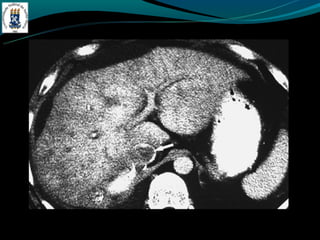

-   TC: densidade menor do que do baço

-   RM: identificar esteatose focal

-Esteatose focal

-   Distribuição segmentar, sub capsular, VB, lig falciforme

-   Margem nítida e em linha reta

-   Não desloca vasos

DOENÇA DO FÍGADOGORDUROSO -E uma resposta uma lesão e a toxina -Acúmulo de colesterol e triglicerídios -Alcoolismo, obesidade, desnutrição, hiperalimentação, costicóide, DM, pancreatite … -Exames de imagem é o melhor método -Avaliação: - TC: densidade menor do que do baço - RM: identificar esteatose focal -Esteatose focal - Distribuição segmentar, sub capsular, VB, lig falciforme - Margem nítida e em linha reta - Não desloca vasos